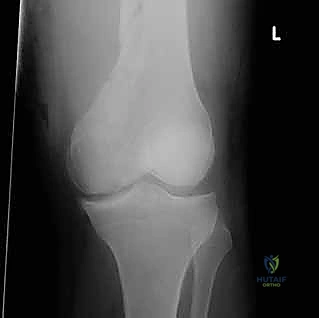

- الأشعة السينية (X-Rays): أخذ صور من زوايا متعددة (أمامي خلفي، وجانبي) لتحديد موقع الكسر ونوعه.

- الأشعة المقطعية (CT Scan): وهي ضرورية جداً في كسور عظم الفخذ البعيدة، خاصة إذا كان الكسر يمتد إلى داخل مفصل الركبة (Intra-articular fractures). تساعد الأشعة المقطعية الدكتور هطيف على بناء نموذج ثلاثي الأبعاد للكسر، مما يسهل التخطيط الجراحي وتحديد أماكن وضع المسامير بدقة.